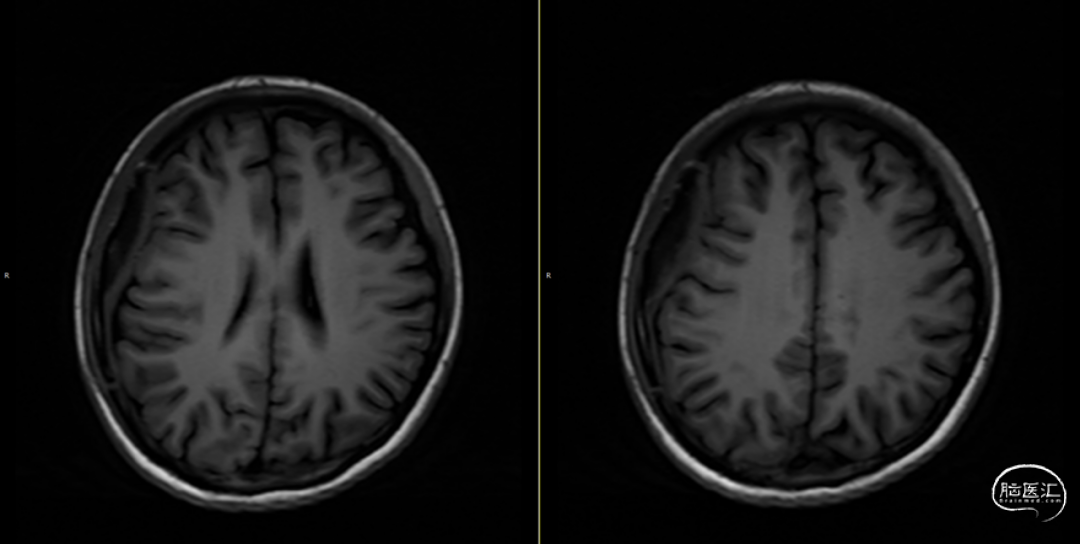

第3次术后16天,复查颅脑MRI(如上图),硬膜外及皮下异常信号较前明显减少,负压引流管引流不明显,拔除负压引流管,继续使用头孢曲松+多西环素口服联合抗炎治疗。

第3次术后23天,拔管后7天复查颅脑(如上图)。

第3次手术后49天,出院后2周复查颅脑CT情况(如上图),刀口愈合正常,患者回归日常生活、学习。